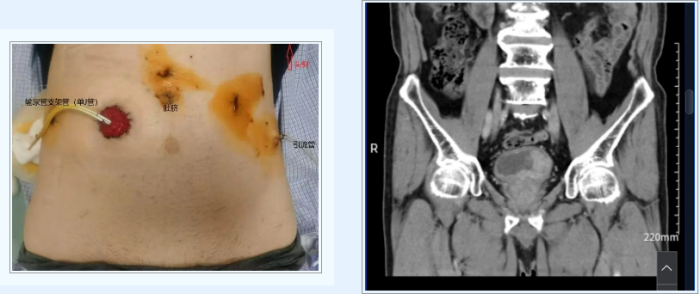

医院组织泌尿外科、麻醉科、肿瘤科等多学科会诊,制定周密手术方案。术中采用腹腔镜技术精准完成膀胱癌根治术及淋巴结清扫,并创新应用“输尿管单孔皮肤造口术”,在保证肿瘤彻底清除的同时,显著减少手术创伤。术后病理证实肿瘤完整切除,患者未出现严重并发症。